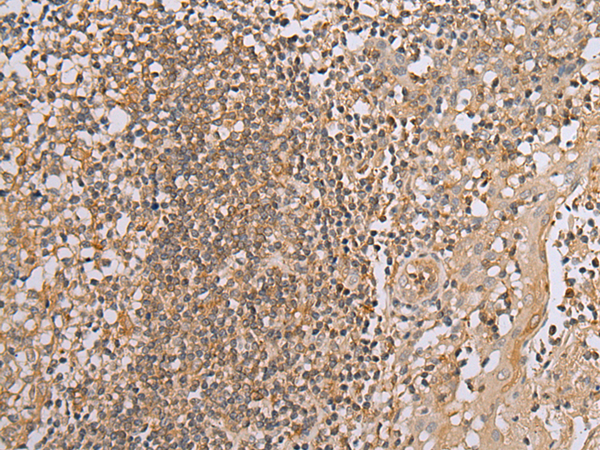

IHC positive control: |

Human tonsil and human esophagus cancer |

IHC Recommend dilution: |

30-150 |